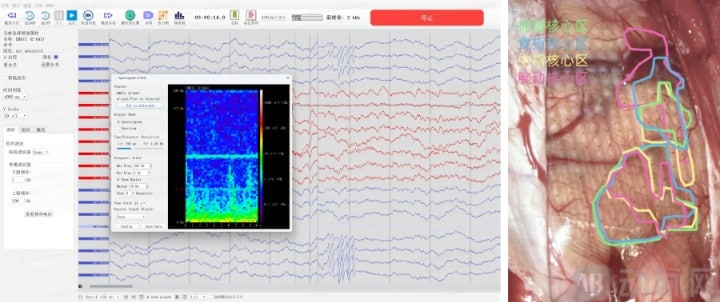

微灵医疗高通量神经电生理采集系统采集电生理信号 (左) 手部精细运动任务功能图谱展示 (右),企业供图

「植入式脑机接口底层就是颅内电生理技术,核心是采集脑内神经电信号,分析信号与行为认知的关系,研究脑的功能与神经环路。」 在科研领域,李骁健与团队也曾使用类似 Neuralink 的针刺式电极,这类电极的核心用途是采集单神经元精度的电生理信号,用于研究单个神经元及神经环路的活动规律,这也是 Neuralink 技术路线的科研起点。

医疗级脑机接口的核心任务在于精准定位 (残存和代偿) 功能区与功能重建。对于脑外科手术患者,脑中既有需要切除的病灶,也有因病灶挤压而畸变但尚存的功能区。在手术中,它可以帮助医生精确区分病灶与畸变功能区。在康复中,它通过建立脑与效应器的信息闭环,引导受损神经环路重塑,达到生理功能的重建。